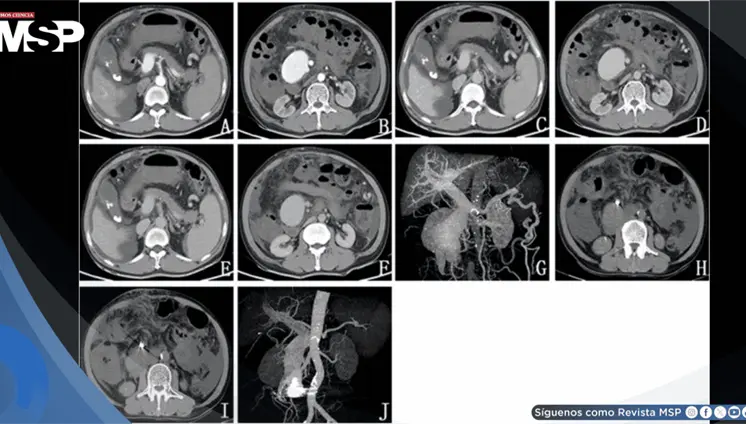

Se confirmó un embarazo intrahepático de 23 semanas, una condición extremadamente rara en la que el feto se desarrolló dentro del lóbulo hepático derecho, con irrigación directa de la arteria hepática y una placenta firmemente adherida al tejido del hígado.

Paciente presenta ruptura intraperitoneal de quiste parasitario después de presión abdominal súbita, manifestando dolor intenso en hipocondrio derecho con irradiación al hombro.

La mujer de 71 años, con antecedentes de histerectomía total y salpingooforectomía izquierda hace 30 años, presentó distensión abdominal progresiva y aumento de peso durante cuatro años.